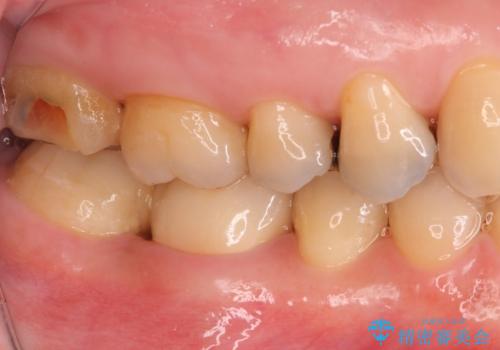

セラミックでの治療をご希望されましたが、残っている歯が少なかったためクラウンでの治療を行いました。

もう一つ奥の歯に関してもセラミックにやり替えたいとのことでしたので、こちらはインレーでの治療を行いました。

- 右下6:仮歯+セラミッククラウン/11,000円+110,000円 右下7:セラミックインレー/77,000円費用は治療当時の料金となります

残る歯が薄かったり、十分な量を確保できない場合はクラウンで治療した方が今後の破折リスクを抑えることができます。